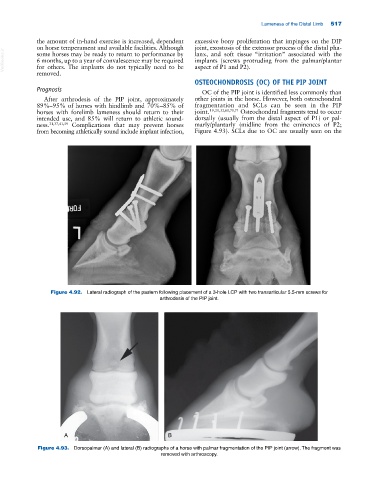

Figure 4.93. Dorsopalmar (A) and lateral (B) radiographs of a horse with palmar fragmentation of the PIP joint (arrow). The fragment was

removed with arthroscopy.